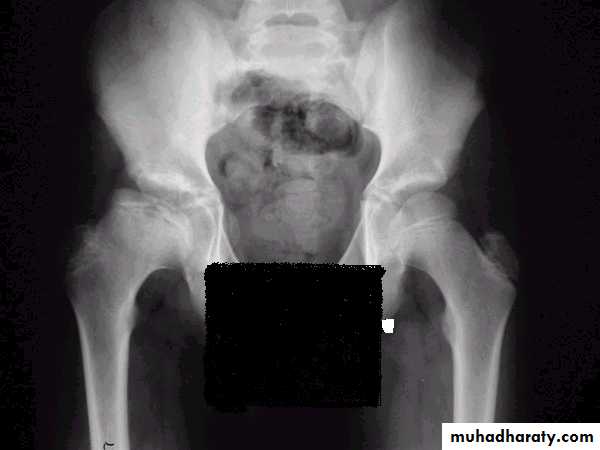

X-ray

1- at the beginning the x- ray look normal some time we can see asymmetry of the ossific centers ; bone scan is helpful at this stage (showing the avascular area) .

2- later on the increase density of the ossific nucleus will be clear ; and there is increase in the joint space .

3- fragmentation of the epiphysis .

4- flattening and lateral displacement of the epiphysis .5- widening of the metaphysis .

6- in sever and advance cases the head become mushroom shape .